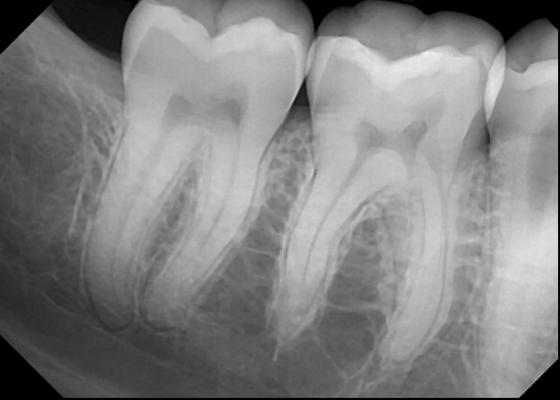

Describe this Radicular Cyst

Epicenter at apex (usually evidence of dental disease or trauma)

Well-defined, corticated

Lucent

Circular

Resorption, Displacement, Expansion (effect on adjacent structures)

Why is this Radicular cyst less circular/oval in this case?